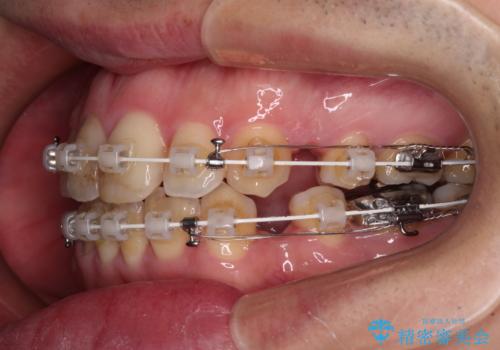

- 矯正装置

- 審美装置

- 治療期間

- 2年6ヶ月

- 治療回数

- 30回以上

口元の突出感を改善するために上下左右の第一小臼歯4本を抜歯し、ワイヤー装置にて矯正治療を行うこととしました。